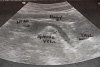

• УЗИ простаты

УЗИ простаты

Предстательная железа имеет форму перевернутой пирамиды, которая находится позади нижней доли лобкового сочленения, кпереди от прямой кишки, книзу и кзади от мочевого пузыря. Верхушка железы, самая